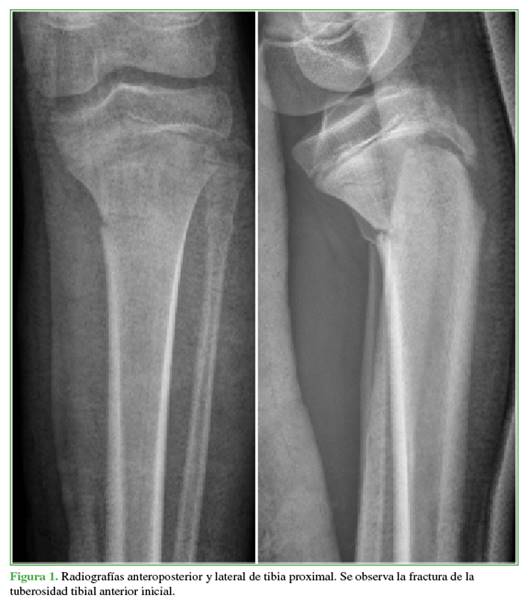

Varón de 14 años que acudió tras una caída con la rodilla en flexión jugando al fútbol, tenía derrame articular, flexo y deformidad en varo de la rodilla. En las radiografías, se visualizó una fractura compleja de la TTA tipo IVB de Ogden (Figura 1).